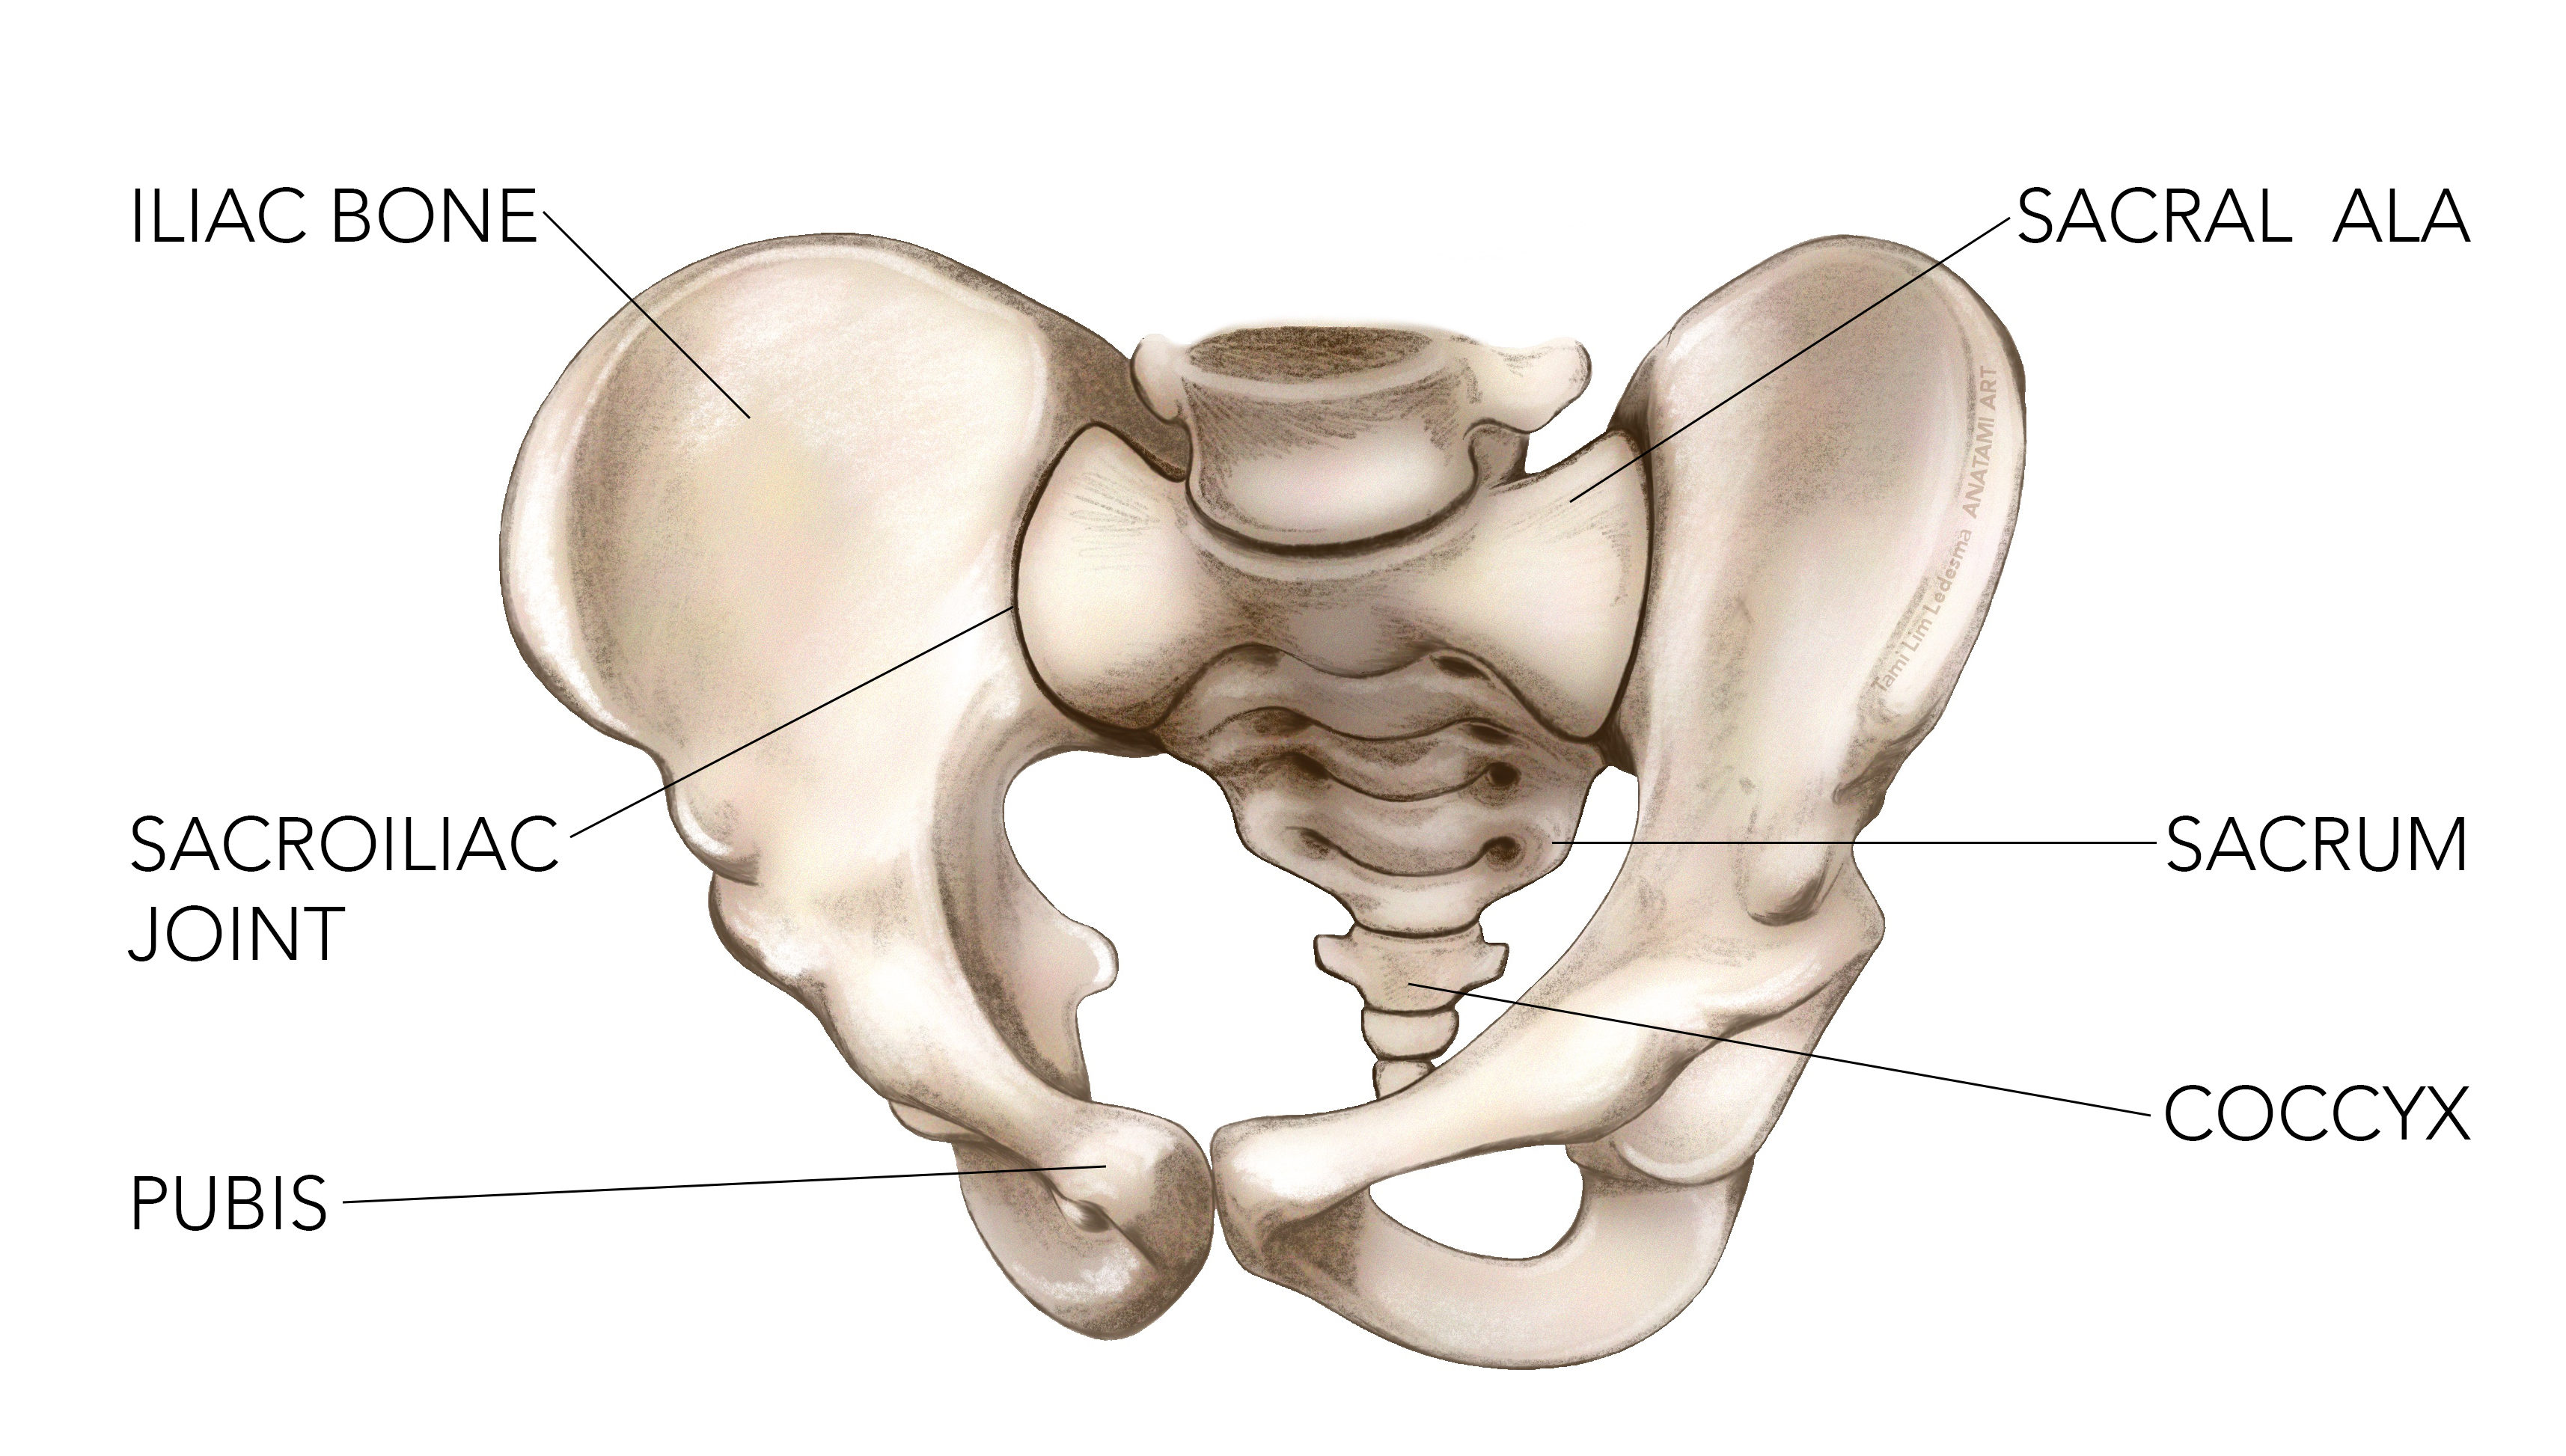

Sacral Fractures Presentation and Treatment Bone and Spine Fracture Du Sacrum Et Sport Il est tout à fait possible de reprendre le sport après une fracture. Découvrez le diagnostic, le traitement et les conséquences de la fracture du sacrum sur votre capacité à marcher. Il convient simplement de prendre quelques précautions. Fractures, or breaks, in this bone are often very painful injuries that can require weeks or months of bed rest to heal.. Fracture Du Sacrum Et Sport.

Les fractures du bassin. Leurs particularités et traitements CHV Fracture Du Sacrum Et Sport Vous souhaitez retourner à l’entraînement après une fracture du pied? Une fracture du sacrum peut survenir en raison d’un accident de la route, d’une chute, d’un sport de contact ou d’une mauvaise. Fractures, or breaks, in this bone are often very painful injuries that can require weeks or months of bed rest to heal. La consolidation d’une fracture du sacrum. Fracture Du Sacrum Et Sport.

Fracture du Sacrum et Marche Conseils et Traitements Efficaces Fracture Du Sacrum Et Sport Following the bed rest, your doctor is likely to prescribe exercises to help. Découvrez le diagnostic, le traitement et les conséquences de la fracture du sacrum sur votre capacité à marcher. Fractures, or breaks, in this bone are often very painful injuries that can require weeks or months of bed rest to heal. Un orthopédiste explique s’il est bon de. Fracture Du Sacrum Et Sport.

Fractures Institut Rennais de Chirurgie Vertébrale IRCV Fracture Du Sacrum Et Sport Une fracture du sacrum peut survenir en raison d’un accident de la route, d’une chute, d’un sport de contact ou d’une mauvaise. Fractures, or breaks, in this bone are often very painful injuries that can require weeks or months of bed rest to heal. La consolidation d’une fracture du sacrum est un processus qui nécessite du temps, de la patience. Fracture Du Sacrum Et Sport.